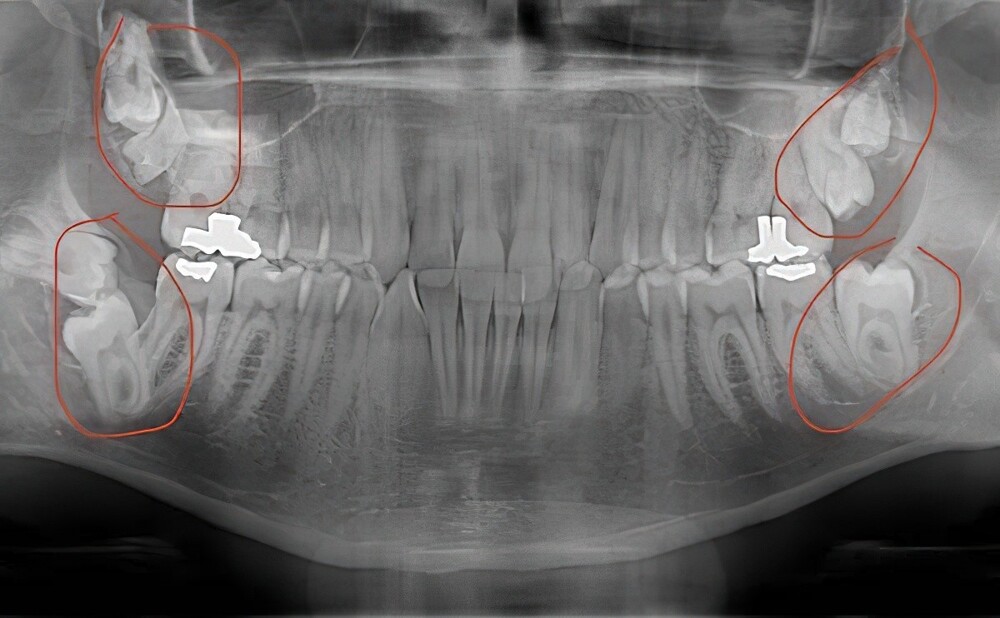

15. A man went to the dentist complaining of pain and found out that he had extra teeth.

- Supernumerary teeth. Should have been cured when you were younger, you would have more opportunities. It can be transmitted by inheritance.